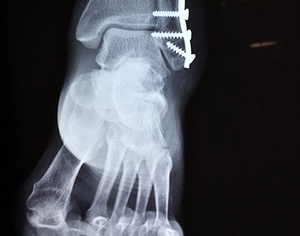

לאחר התאונה הנפגע פונה לבי"ח קפלן שם נמצא כי נגרם שבר לקרסול רגל שמאל שגובס. התובע נבדק ע"י ועדה רפואית של המוסד לביטוח לאומי אשר בדקה את התובע וקבעה לו נכות לצמיתות בשיעור של 19%.